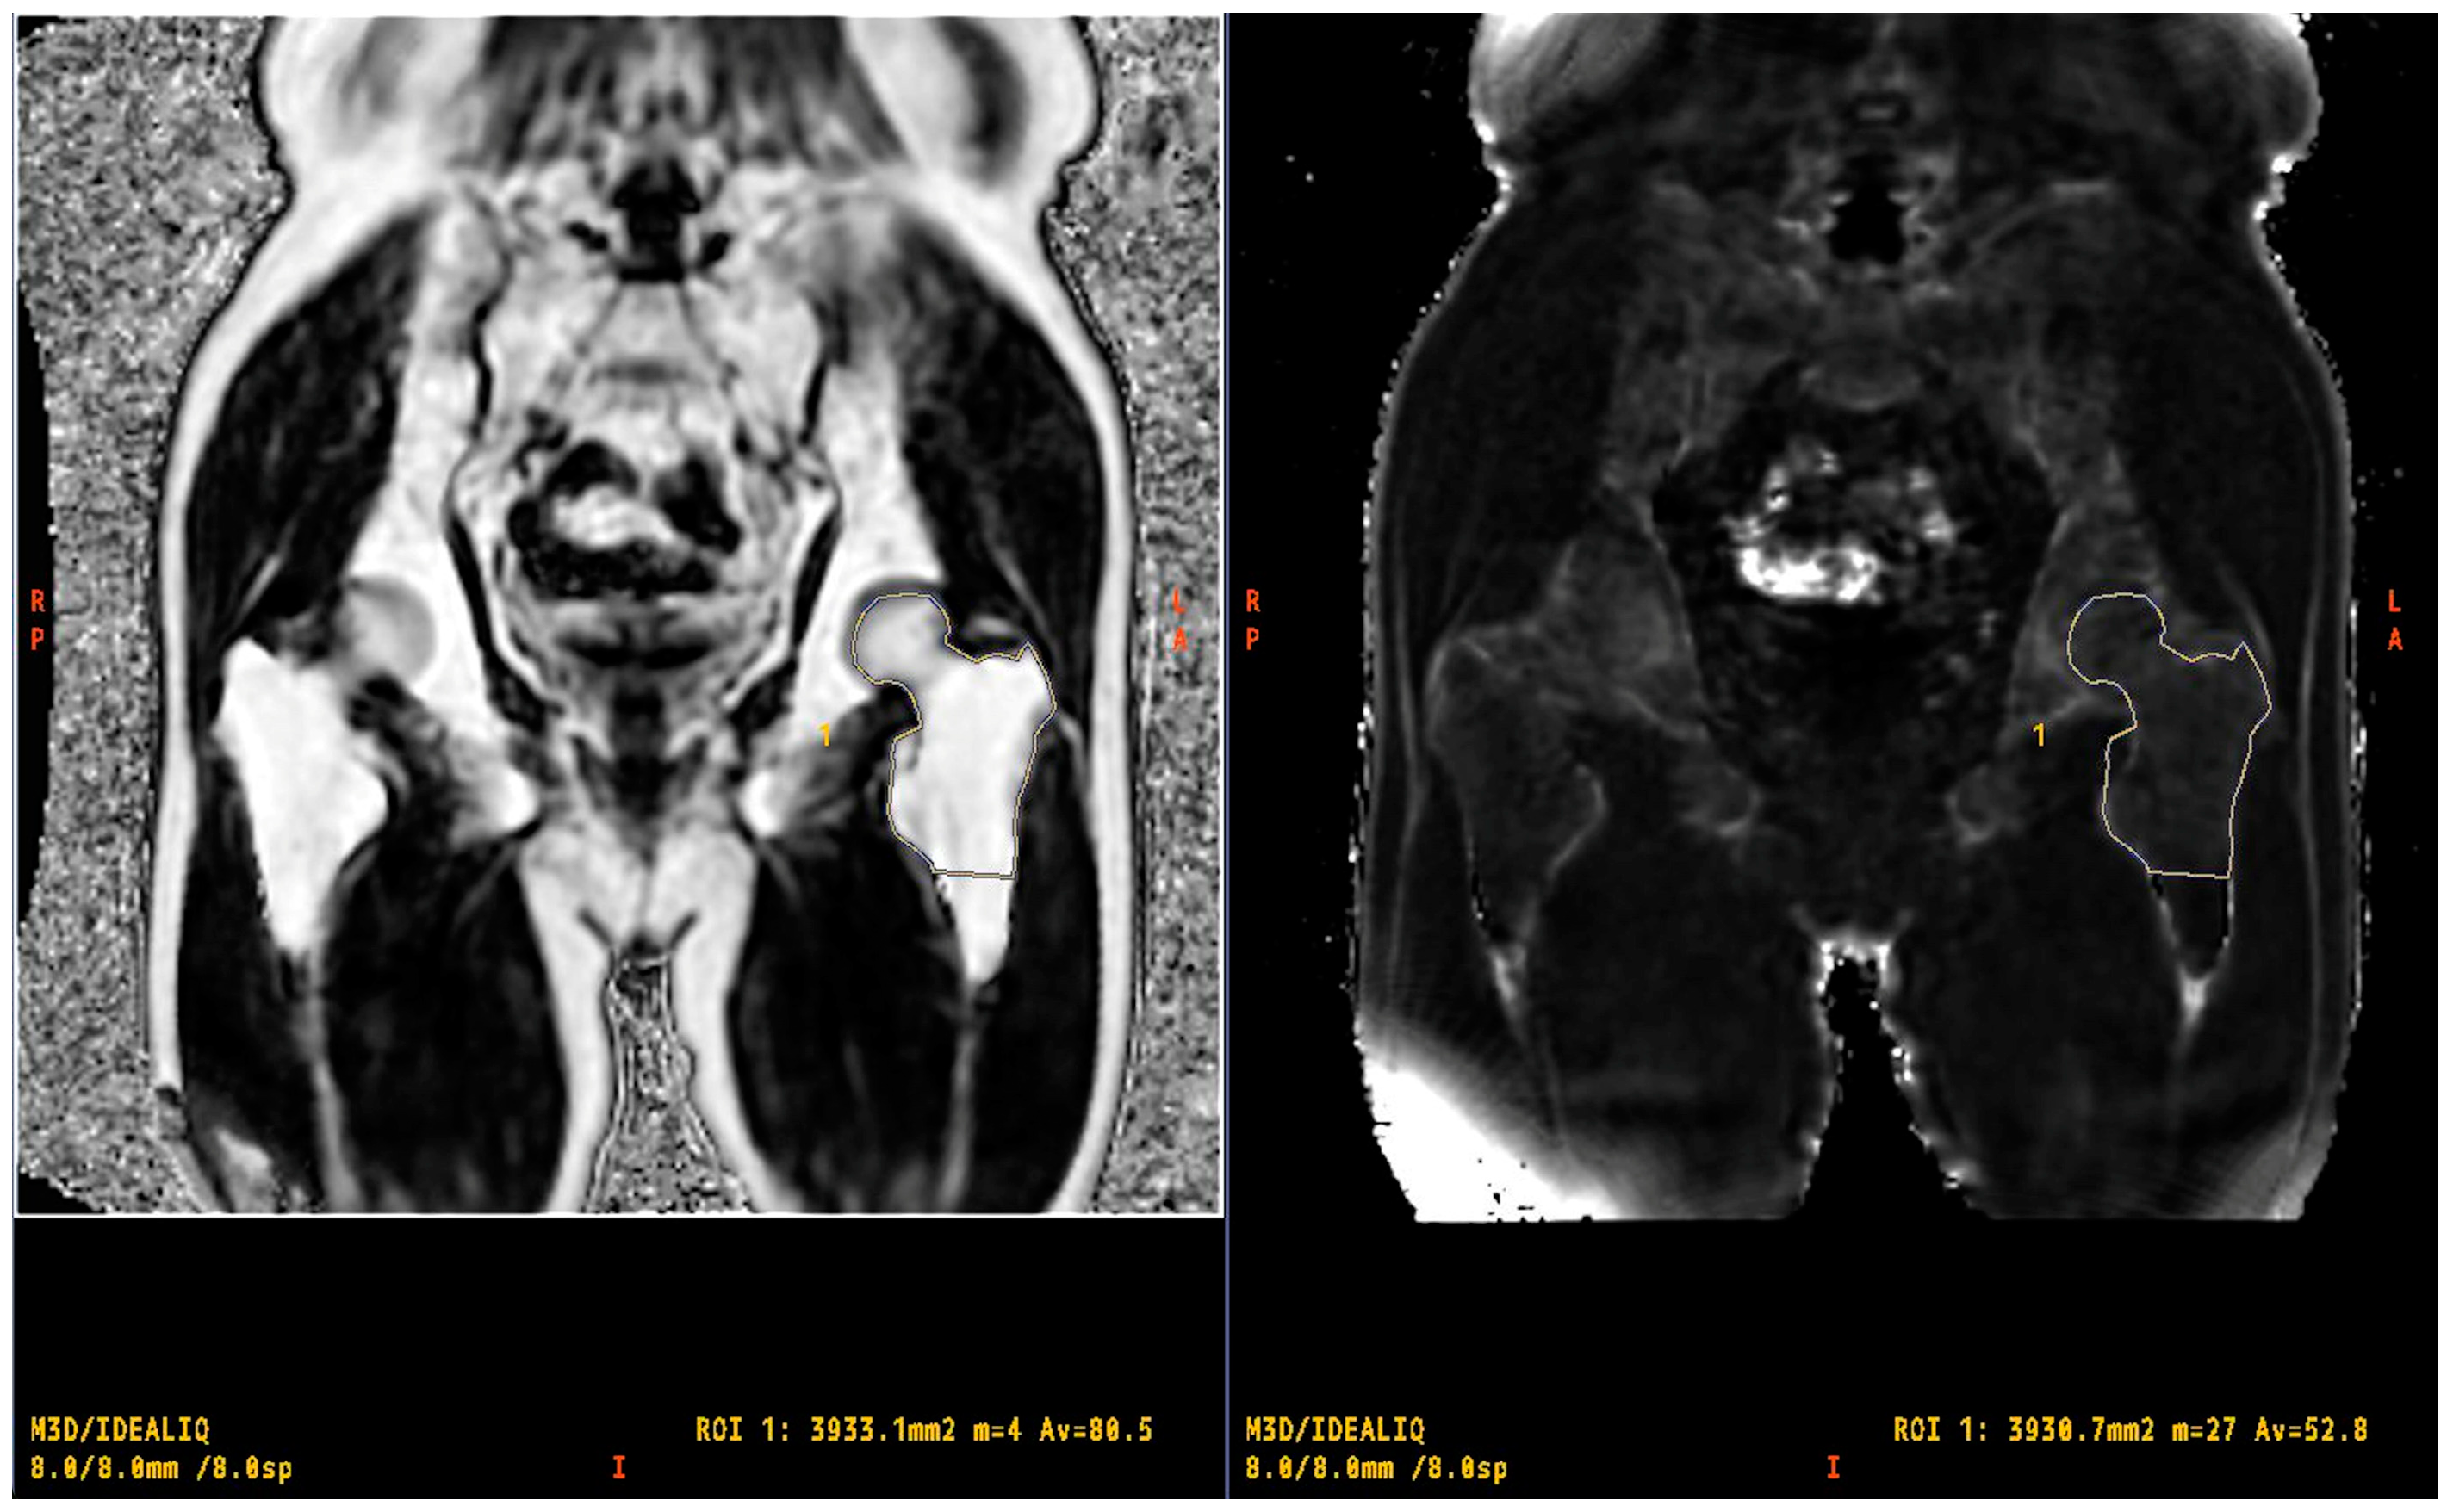

2.4. Evaluation of R2* and PDFF

2.5. Statistical Analysis